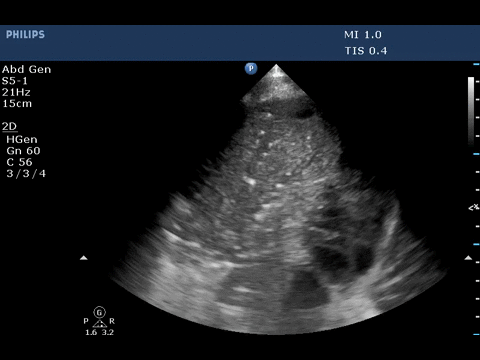

The ultrasound image above shows dynamic air bronchogram.

Air bronchogram is described as a punctiform or linear hyperechoic

artifacts within the consolidation. It is considered dynamic if there is

>1mm movement with air entry and is due to centrifugal movement of

gas bubbles in bronchus, a sign of airway patency. The specificity and

positive predictive value of dynamic air bronchogram in presence of

alveolar consolidation to predict pneumonia is 94% and 97% respectively.